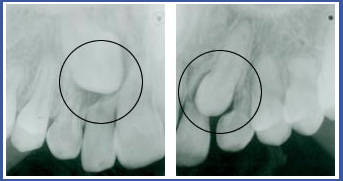

שיניים כלואות

יש מצבים בהם שן לא מצליחה לבקוע למקומה בקשת השיניים ונשארת כלואה בחניכיים.

1. כליאה עקב צפיפות בקשת השיניים: המקום לבקיעת השן הצטמצם ואין לה מקום לבקוע. במקרה כזה השן תבקע לעמדה לא נכונה או שתישאר כלואה בחניכיים.

2. חסימה למסלול הבקיעה: למשל שן עודפת באזור, חוסר ספיגה של שורש שן החלב.

3. טעות במסלול הבקיעה: שן קבועה מתחילה את התפתחותה בעומק החניכיים ועם הזמן מתחילה לבקוע.שיניים שלהן מסלול בקיעה ארוך עלולות "לטעות" וכתוצאה יישארו כלואות בחניכיים במיקום לא נכון. מצב כזה אופייני בעיקר לניבים עליונים להם מסלול בקיעה ארוך מאד (כליאה כזו קיימת גם בשיניים אחרות בשכיחות נמוכה יותר). שכיחות כליאה של ניב עליון באוכלוסיה 1%-3%.

- לפני טיפול – השן הכלואה אינה נראית בחלל הפה